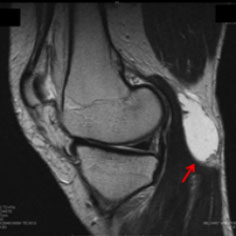

ベーカー嚢腫の診断には、詳細な病歴聴取と身体診察が基本となります。膝の後部に特徴的な腫れが見られる場合、多くの臨床医はベーカー嚢腫を疑います。触診により、柔らかく弾力のある腫瘤が確認されることが一般的です。しかし、正確な診断には画像診断が不可欠です。まず、超音波検査は嚢腫の存在を確認するための非侵襲的かつ迅速な方法として広く用いられています。さらに、MRIは嚢腫のサイズや位置、内部構造を詳細に評価するために有用です。また、MRIは膝関節の他の病変や嚢腫の基礎疾患を特定するのにも役立ちます。必要に応じて、関節液の分析を行い、感染症や結晶誘発性関節炎の可能性を排除することも考慮されます。